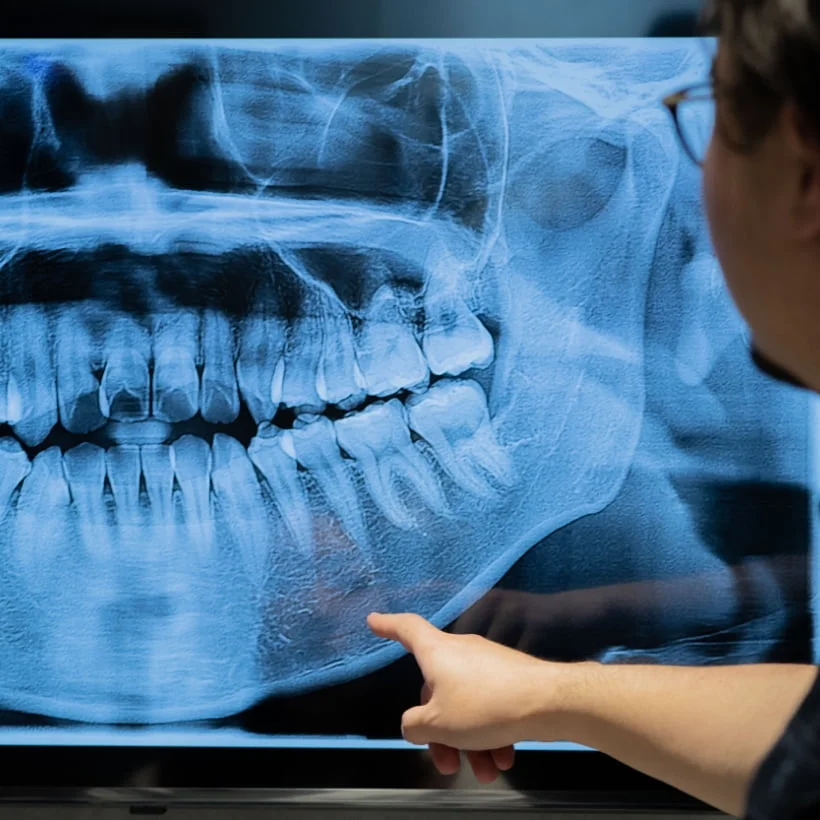

口腔外科・矯正歯科認定医が在籍。精密な診査診断に基づき、患者様に寄り添いご提案します。